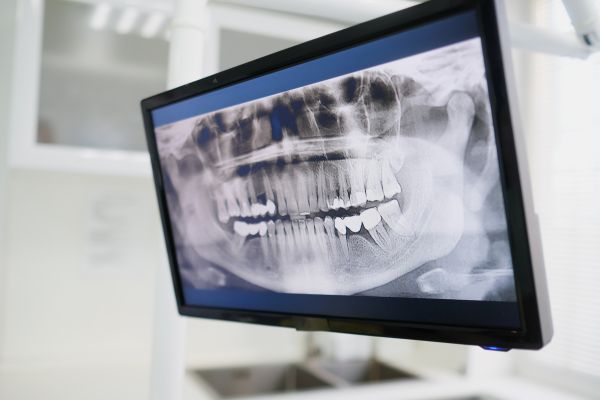

Бързата загуба на зъби в напреднала възраст е свързана с повишен риск от смърт, сочи проучване, ръководено от изследователи от Университета „Съчуан“, Китай. Констатациите, публикувани в списанието BMC Geriatrics, подчертават важността на поддържането на добро орално здраве и предполагат, че загубата на зъби може да бъде ключов индикатор за други сериозни здравословни проблеми.

Въпреки че загубата на зъби с възрастта често е неизбежна, нейното въздействие може да бъде широкообхватно. Тя не само влияе върху качеството на живот, като затруднява дъвченето и намалява насладата от храненето, но е свързана и с по-висока смъртност (не само обща смъртност, но и от специфични причини като сърдечни заболявания, рак на белия дроб и пневмония).

Повечето проучвания, изследващи връзката между загубата на зъби и риска от смърт, са фокусирани върху броя на зъбите в даден момент, без да отчитат промените във времето. Настоящото проучване е първото, което цялостно оценява връзката между загубата на зъби с течение на времето и смъртността в голяма кохорта от възрастни хора.